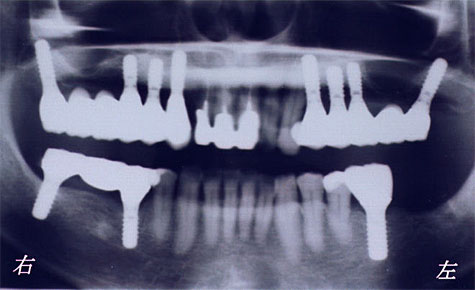

下のレントゲン写真が治療後の状態です。

このように インプラントの傾斜埋入を行うと、サイナスリフトや骨の移植手術を行わないで治療を行えます。

しかし、インプラントを斜めに埋入する部位が存在しなければ もちろん行えません。

左のレントゲン写真が全体像で右のレントゲン写真が

インプラント部分のみの拡大像です。

クリックすると拡大されます。